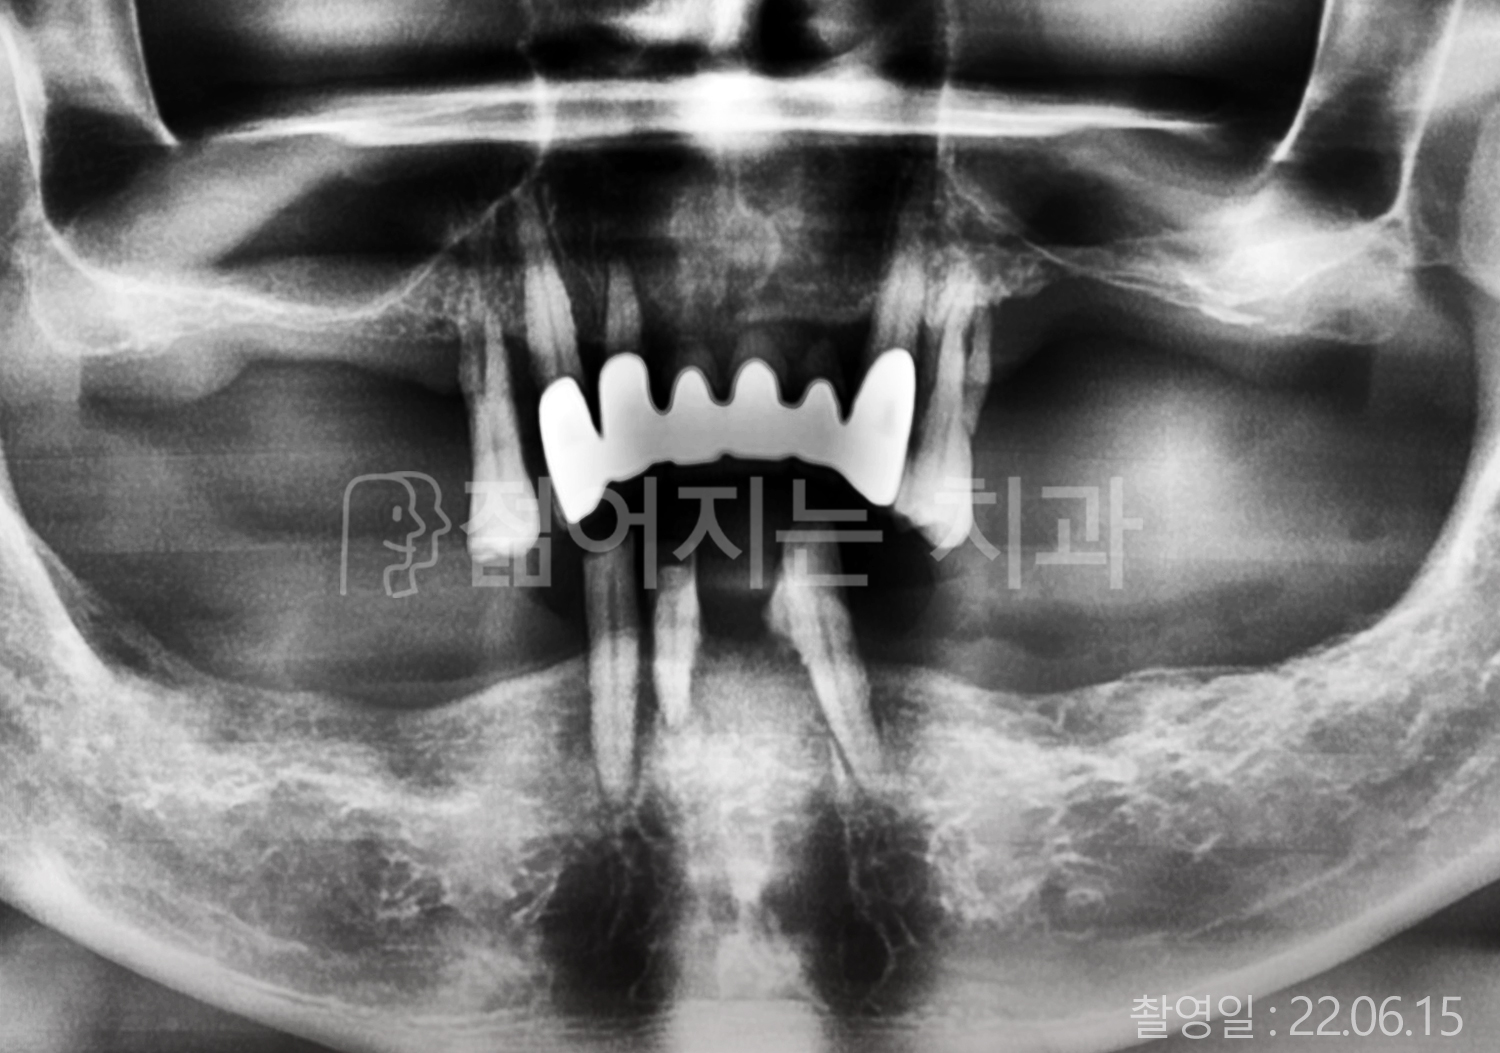

• 50대 고혈압, 고지혈증 전체치아 10개 이상 임플란트